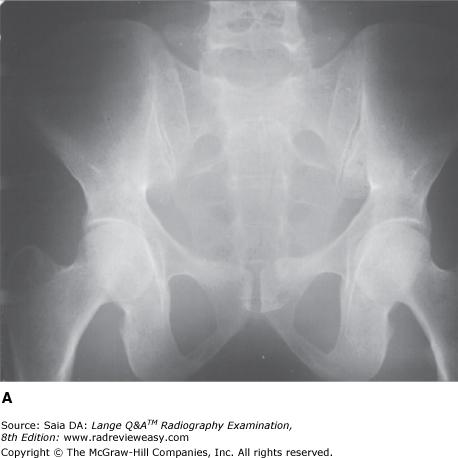

Which of the following statements is (are) most likely true regarding the figure below?

1.Image A was made using a higher kVp than image B.

2.Image A was made with a higher ratio grid than image B.

3.Image A demonstrates shorter scale contrast than image B.

A 1 only

B 1 and 2 only

C 2 and 3 only

D 1, 2, and 3

-Image A was made using 80 kVp at 75 mAs; Image B was made using 100 kVp at 18 mAs; all other exposure factors remained the same. As kVp is increased, the percentage of scattered radiation relative to primary radiation increases, hence the grayer appearance of image B. Use of optimal kilovoltage for each anatomic part is helpful in keeping scatter to a minimum. The production of scattered radiation will also be limited if the field size is as small as possible. A grid is the most effective way to remove scattered photons from those exiting the patient. Grids are designed to selectively absorb scattered radiation while absorbing as little of the primary radiation as possible. Images produced with higher ratio grids will possess fewer grays than those made with lower ratio grids.